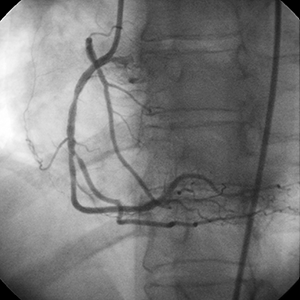

"Esta RCA altamente estenosada contenía un grado significativo de calcio que no podría apreciarse plenamente en el momento de la angiografía. Cabe destacar que el segmento calcificado no se encontraba en la región de estrechamiento más crítico. Sin embargo, la lesión calcificada no se pudo dilatar después de la aplicación del stent.

Si la dilatación previa del vaso se hubiese realizado antes de la aplicación del stent, la necesidad de usar el sistema Rotablator™ habría sido obvia, y posiblemente se habría evitado la dificultad que se encontró al tratar este vaso."